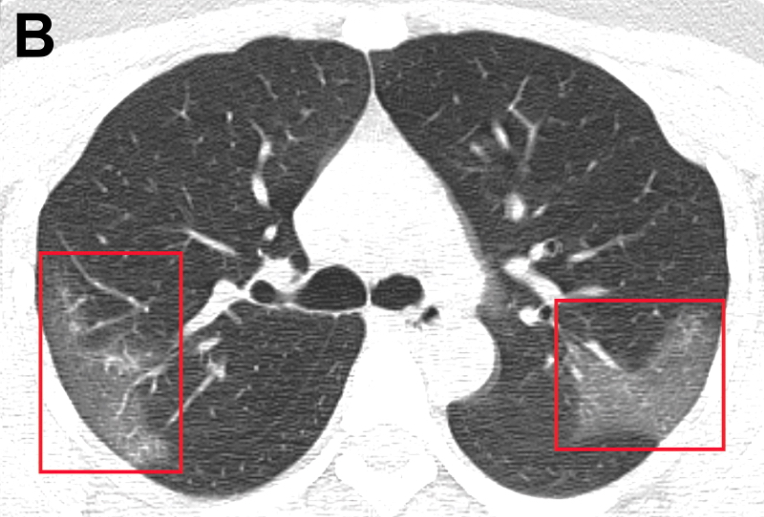

La mortalidad de pacientes críticos con neumonía por COVID-19 es considerable. El tiempo de supervivencia de los no sobrevivientes es de 1 a 2 semanas tras el ingreso en la UCI. Los pacientes mayores (> 65 años) con comorbilidades y síndrome de dificultad respiratoria aguda tienen un mayor riesgo de muerte. La gravedad de la neumonía por COVID-19 plantea una gran presión sobre los recursos de atención crítica en los hospitales, especialmente si no cuentan con el personal o los recursos adecuados.  Lancet Resp Med, 24 de febrero de 2020